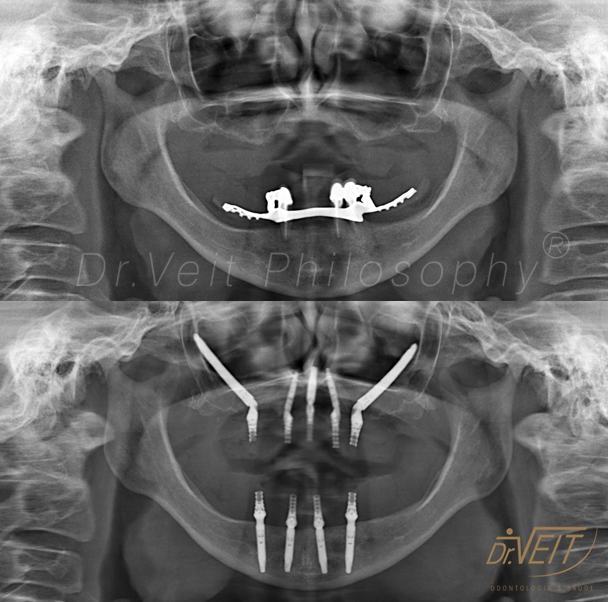

Arte de reabilitar os casos “impossíveis”. Pacientes que buscam a reabilitação oral podem conquistar um belo sorriso com segurança, mais conforto e tranquilidade com o uso do Implante Zigomático. A técnica possui o diferencial de realizar a implantação no osso zigomático e é indicada para casos de perda óssea maxilar avançada.